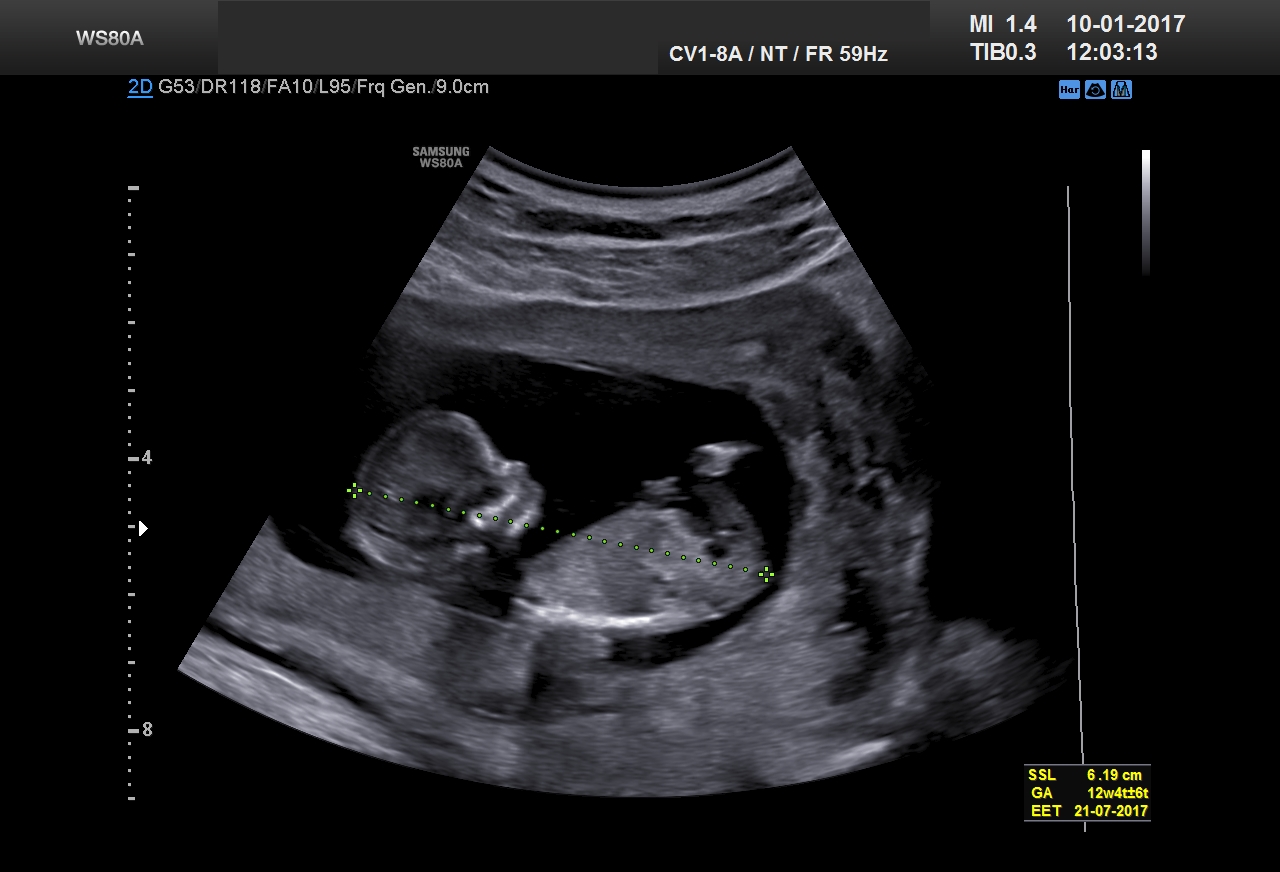

Der Winzling in diesem Video einer Ultraschall-Kontrolle in der 12. Schwangerschaftswoche misst ca. 5 Zentimeter – und winkt er uns «Baby-TV-Guckern» da etwa zu? Die Aufnahme entstand in der Praxis Gyné am See in Küsnacht ZH.

Grösse des Fötus (Scheitel-Steiss-Länge): 45-53 mm

Gewicht: 15 g

Im Ultraschall sieht man es deutlich: Der Fötus bewegt sich. Langsames Beugen und Strecken der Wirbelsäule übt er seit mehreren Tagen. Nun werden diese Bewegungen immer feiner. Er öffnet den Mund zu einem Gähnen, bewegt seine Zunge. Streckt seine Arme und Beine. Voraussetzung dafür ist ausreichendes Muskelwachstum, überdies müssen Gehirntätigkeit und Muskelarbeit aufeinander abgestimmt werden.